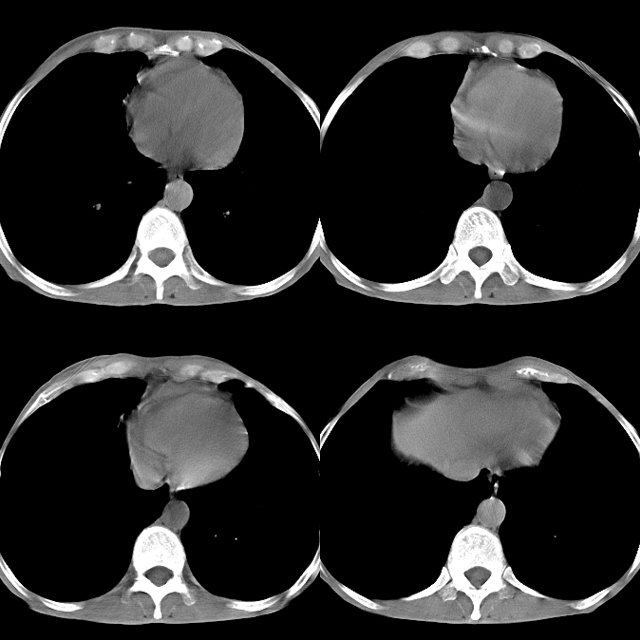

以下是引用心路寻觅在2010-4-17 18:35:00的发言:[br]纵膈多组淋巴结肿大呈“冰冻纵膈”,左肺上叶空洞伴其内结节密度影,考虑淋巴瘤伴左肺上叶曲霉菌感染。[br][br][本贴已被 心路寻觅 于 2010-4-17 18:36:23 修改过]

以下是引用zhangzhongshou在2010-4-17 19:32:00的发言:[br]一元论考虑左肺空洞型肺癌并纵隔淋巴结转移可能性大。